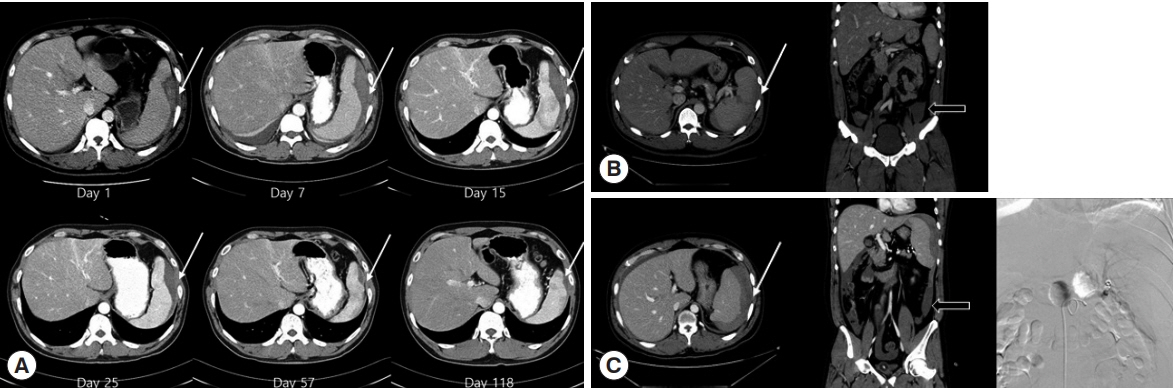

A 39-year-old man visited our hospital (Inha University Hospital, Incheon, Korea) with a febrile sensation since 1 week prior. On physical examination, his blood pressure was 120/80 mmHg, pulse rate was 80/min, respiratory rate was 20/min, and body temperature was 39°C. He had severe left upper abdominal pain and splenomegaly. On laboratory examination, he presented decreased hemoglobin (12.3 g/dl) and platelet count (22,000/μl). His prothrombin time (PT) was 1.00 (international normalized ratio, INR), activated partial prothrombin time (aPTT) was 41.0 seconds, total bilirubin was 2.5 mg/dl, and P. vivax parasitemia was 42,174/μl (Table 1). He was diagnosed with vivax malaria using rapid antigen testing (SD-Bioline Malaria-Ag-Pf/Pan™) and peripheral blood smear. Abdominal computed tomography (CT) was done for the evaluation of painful splenomegaly and showed subcapsular hemorrhage without splenic rupture. His hemoglobin decreased from 12.3 to 9.6 after 2 days, but vital signs were stable. He was observed without surgery or intervention. The patient was treated with chloroquine and primaquine, and he gradually improved and was discharged. Follow-up abdominal CT was performed on the 7th, 15th, 25th, 57th, and 118th day after first diagnosis (Fig. 1A).

In summary, the above case showed subcapsular hemorrhage without splenic rupture. The patient experienced relatively rapid improvement with anti-malarial drugs, indicating the possibility that spleen capsule tension can be improved rapidly. Therefore, medical treatment and close observation can be considered a treatment option in the subcapsular hemorrhage stage. In addition, this case illustrated interesting changes and improvement in subcapsular hemorrhage with time, as seen in 6 CTs performed over 4 months.

A 40-year-old man was admitted to a hospital in Incheon with fever and abdominal pain for the prior 5 days. He presented stable blood pressure and heart rate. His initial hemoglobin was 14.2 g/dl, platelet count was 35,000/μl, PT was 1.02 (INR), aPTT was 34.6 sec, and total bilirubin was 2.5 mg/dl. He showed a positive result in the malaria rapid antigen test (SD-Bioline Malaria-Ag-Pf/Pan™), and P. vivax was seen in a peripheral blood smear. He was immediately treated with chloroquine. However, the next day he experienced more severe abdominal pain and was transferred to our hospital. At the time of the visit to our hospital, his blood pressure was 133/63 mmHg, pulse rate was 96/min, respiratory rate was 18/min, and body temperature was 39.6°C. He was clearly conscious and there was no tendency of bleeding found in the mouth, anus, or urine. His hemoglobin was 13.4 g/dl (Table 1). He underwent CT for evaluation of the severe right upper abdominal pain, and splenic rupture was found with multifocal splenic infarction and subcapsular hemorrhage (Fig. 1B). The patient's vital signs were stable, and the patient did not want to undergo any surgery or intervention. After 2 days, the patient's hemoglobin dropped to 10.8. However, his vital signs were stable with no hypotension. On the 4th day, he was transferred out to another hospital uneventfully, and he is alive with no further problems 3 years later.

A 38-year-old man visited our hospital [6]. He had undergone chemotherapy for extranodal marginal zone B-cell lymphoma of mucosa-associated lymphoid tissue and had no subsequent evidence of disease. When he visited our hospital, his blood pressure was 120, pulse rate was 80/min, respiratory rate was 20/min, and body temperature was 39°C. He presented a platelet count of 71,000/μl, serum bilirubin of 1.9 mg/dl, PT of 1.22 (INR), aPTT of 35.4 sec, and 14,019/μl of parasitemia (Table 1). Through rapid antigen testing (SD-Bioline Malaria-Ag-Pf/Pan™) and peripheral blood smears, he was diagnosed with vivax malaria. CT was performed for severe upper abdominal pain, and subcapsular hemorrhage of spleen and hemoperitoneum were seen on CT (Fig. 1C). The patient’s hemoglobin level was 14.4 g/dl on the first day and dropped to 9.5 the next day. He had continuous hypotension, and spleen angiography was conducted. There was no apparent extravasation of the contrast agent and embolization was performed. The patient was stable and there was no additional bleeding on CT 6 days later. After 8 days, CT showed no progression of hemorrhage. Subsequently, he was discharged without any further problems.